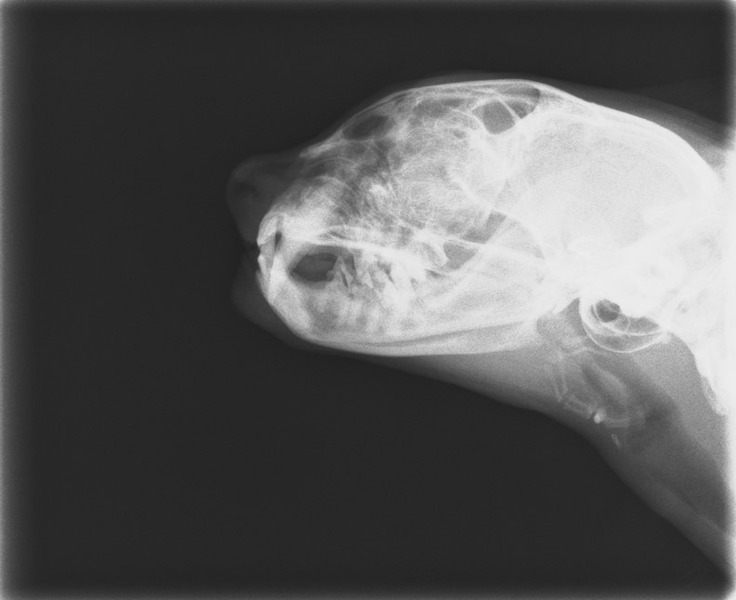

また今日はレントゲンもとりました。

肺の状態も心配だったのですが、

特に悪そうな感じもなく、ほっと一安心しました。